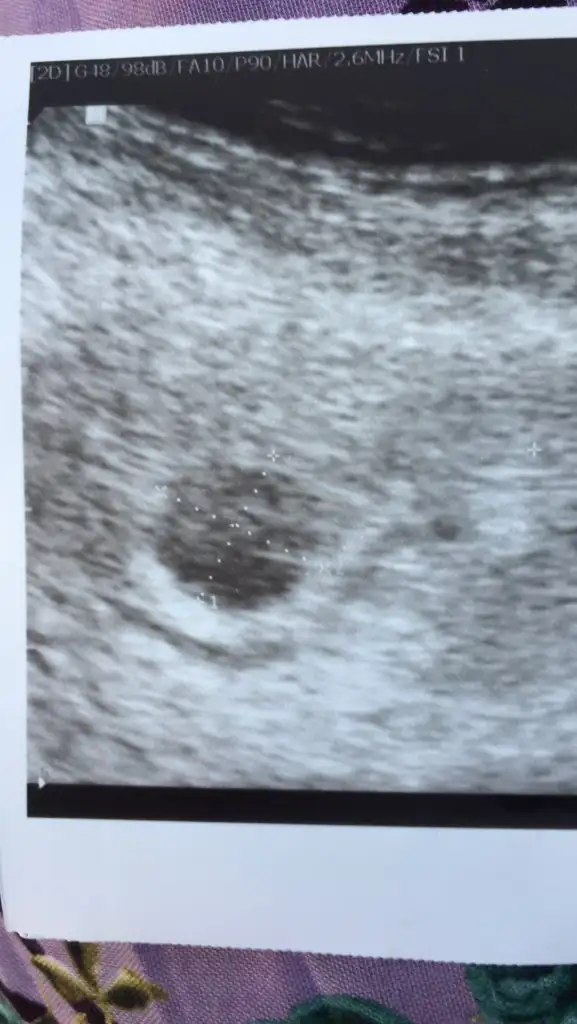

Ben de doktora gittim sabah kontrolüm vardı 12 mm olmuş kese kalp atışı görmedi 15-20 gün sonra gel dedi ultrasonu pek iyi değil sanırım kızımda 6+0 da görmüştüm kalp atışınıEki Görüntüle 2657406